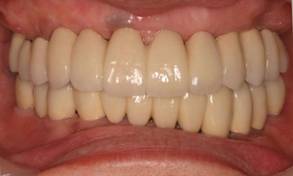

術後。上部構造はハイブリッドレジンです。しっかり嚙めるようになり喜んでいただきました。

上部構造装着後6年。ハイブリッドレジンを使用したため、少し艶がなくなってきました。上部構造の材料には金属、ハイブリッドレジン、セラミックなどがあります。セラミックはきれいですが欠けやすいため、最近はフルジルコニアを使っています。